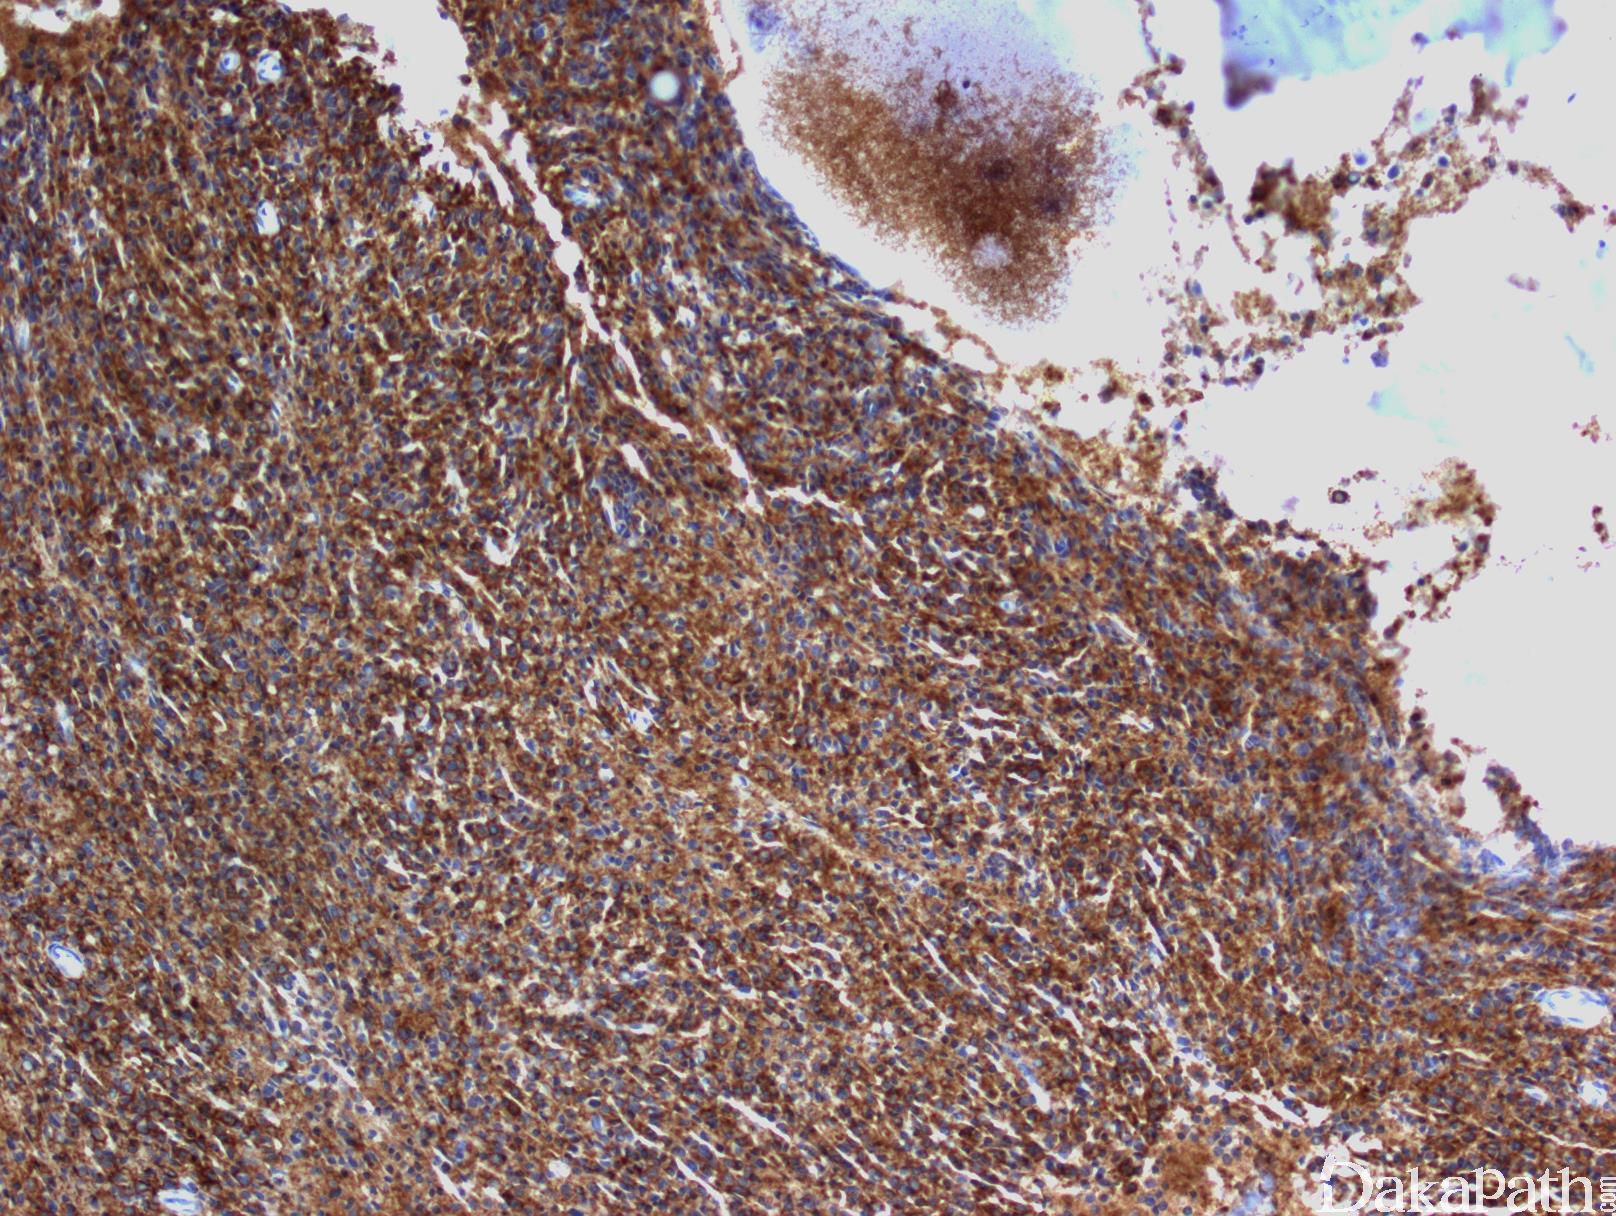

浆细胞表达 CD138. 胞浆内 kappa 或 lambda,但无限制性表面轻链。CD19 和 CD20 一般阴性,但少数病例 CD20 有表达或部分表达。有些病例 cyclin D1+, 多见于类似淋巴浆细胞样形态的浆细胞骨髓瘤。异常表达的抗原(正常浆细胞不表达或仅少数细胞表达)有:CD56(见于 75-80%病例)、CD200(60-75%)、CD28(40%)、KIT(20-35%)、CD20(10-20%)。